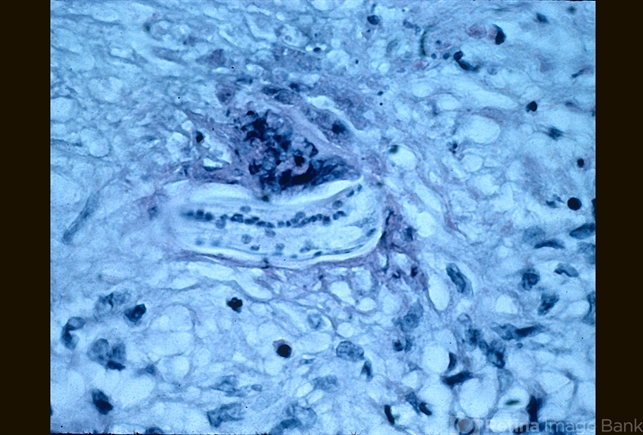

- nematode granuloma, larva

- High power pathology of larva.